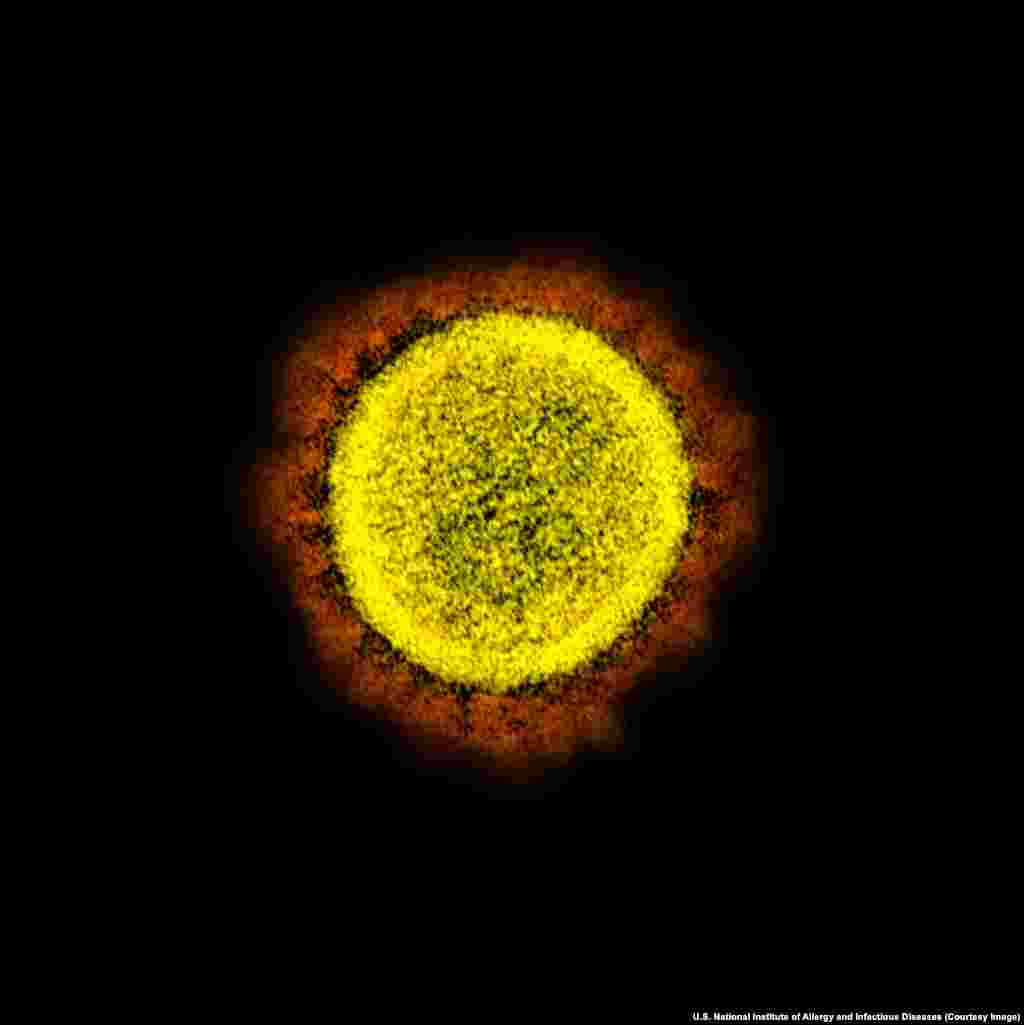

4

Pamje e koronavirusit. Koronaviruset kanë marrë këtë emër për shkak të pamjes që kanë si kurorë kur shihen me mikroskop. "Korona" është shprehje latine për kurorë.